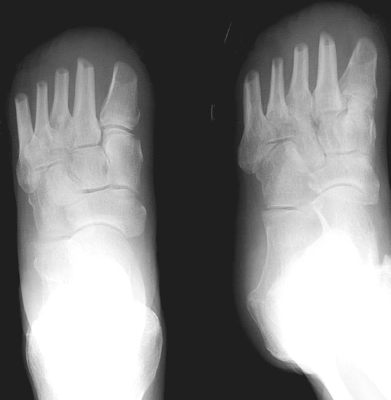

Another transmetatarsal amputation.